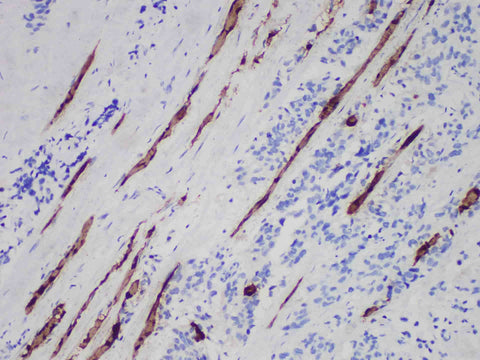

Myoglobin Monoclonal Antibody Stored at 2~8°C

Applications IHC-P

Tissue Specificity rhabdomyosarcoma

Myoglobin, also known as myosin, with a molecular weight of about 17.8kda, is a specific protein for striated muscle. It is mainly used for the diagnosis and differential diagnosis of rhabdomyoma